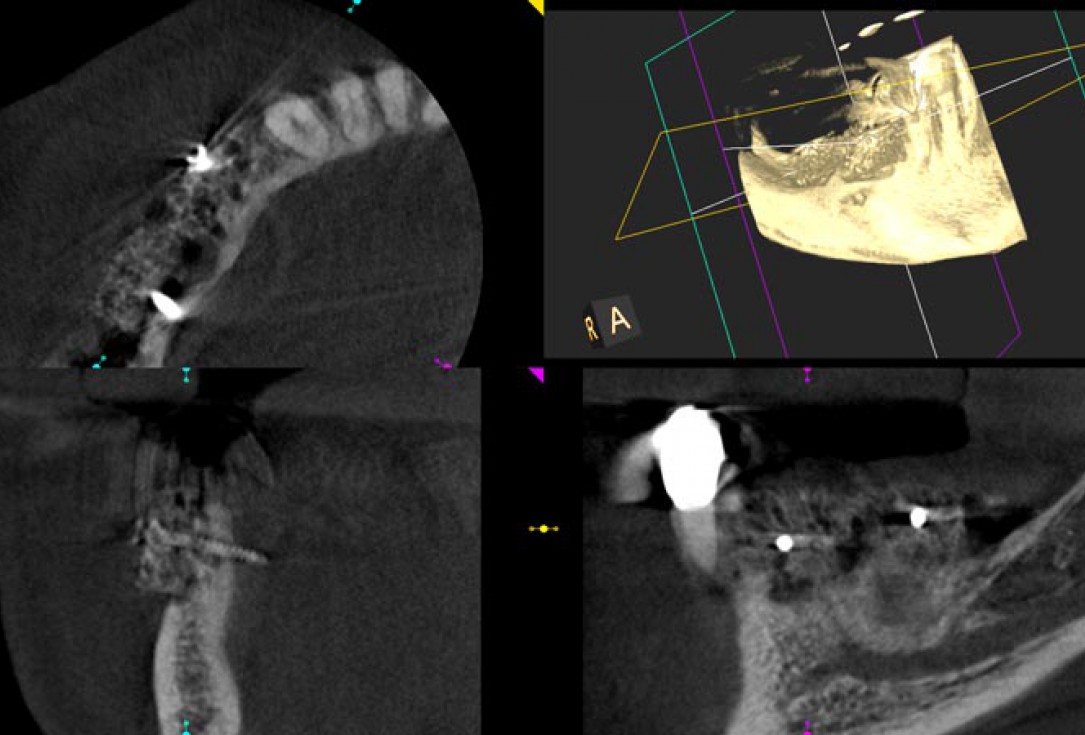

03/14 - Initial CBCT scan showing severe ridge atrophy in the right mandible

Block augmentation with maxgraft® in the mandible - PD Dr. Dr. F. Kloss